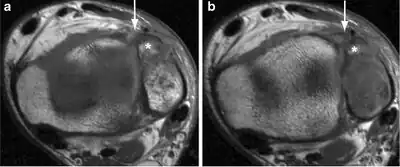

| a, b)Image demonstrates the avulsion fracture of the anterior aspect of the fibula (Wagstaffe–Lefort, asterisk), with a discontinuous aspect of the anterior distal tibiofibular ligament | |

Le Fort's fracture of the ankle is a vertical fracture of the antero-medial part of the distal fibula with avulsion of the anterior tibiofibular ligament,[1] opposite to a Tillaux-Chaput avulsion fracture